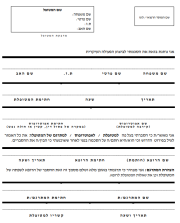

| 20:31, 27 בינואר 2024 | IAPWG protocol.png (קובץ) |  |

131 קילו־בייטים | Roeitul | 1 | |